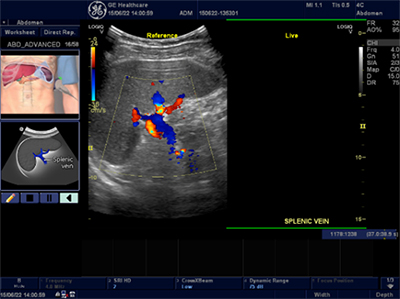

続いて,医療法人松尾クリニック理事長 松尾汎氏が血管エコーの実際を紹介し,「超音波診断は,抽出した画像を観察し,臨床に活用するという段階まで使うことができます。例えば,頚動脈エコーにより動脈硬化の進行具合を診て,生活習慣病の診断にも活用することも可能となります」と,今後の開業医による超音波診断の活用に期待を寄せた。

さらに当日は,両氏が会場で使用した汎用超音波診断装置“LOGIQ”の新モデル「LOGIQ V5(ロジック ブイファイブ)」の製品特徴と機能も紹介された。「LOGIQ V5」は,地域の健康と診療を支える開業医のニーズに対応するソリューションを搭載した新製品。コンパクトでありながら高画質と高機能を保ち,スピーディーな診断を実現する。